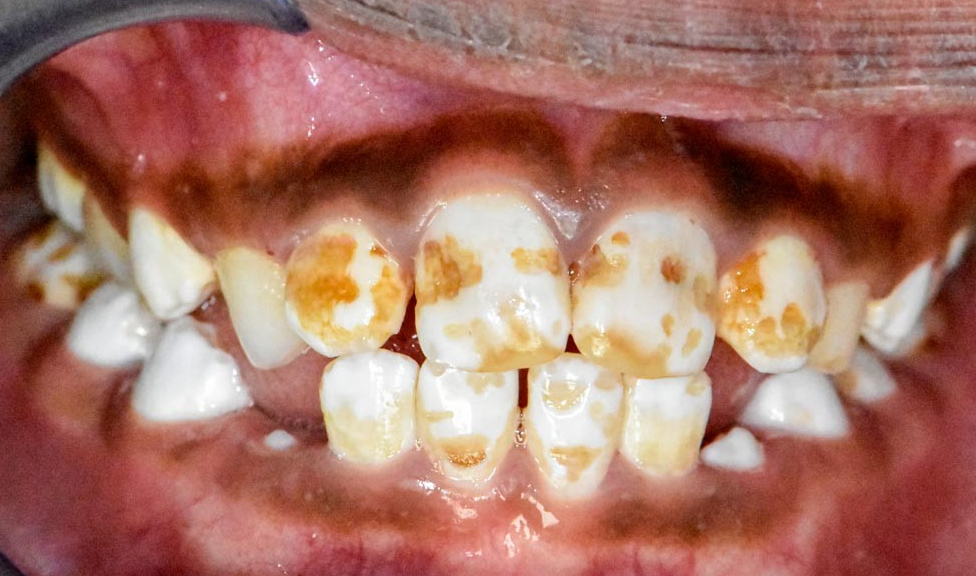

Fluorose dentaire — Peut être discrète, modérée ou sévère selon le niveau d’exposition au fluor. Elle se distingue d’autres anomalies par des lésions symétriques sur les dents.

La MIH : une “épidémie silencieuse” chez les enfants

La hypominéralisation molaire-incisive (MIH) est devenue un sujet de préoccupation croissante en odontologie pédiatrique. Selon la Revue du Praticien, elle touche 1 enfant sur 7 au niveau mondial, avec une prévalence estimée entre 15 et 20 % des enfants selon certaines études.

La MIH se traduit par un défaut qualitatif de l’émail sur au moins une des quatre premières molaires permanentes, associé ou non à une atteinte des incisives. Les symptômes incluent des taches blanches, jaunes ou brunes, une hypersensibilité aux stimuli thermiques, et un risque accru de caries.

Facteurs suspectés : infections respiratoires ou oto-rhino-laryngologiques dans la petite enfance, complications périnatales, et possiblement l’utilisation d’antibiotiques (comme l’amoxicilline) entre 0 et 4 ans.

Le dépistage précoce est capital : les enfants atteints nécessitent en moyenne 10 fois plus de traitements dentaires que les autres. Une visite régulière chez le dentiste dès l’apparition des premières molaires permanentes (autour de 6 ans) est fortement recommandée.